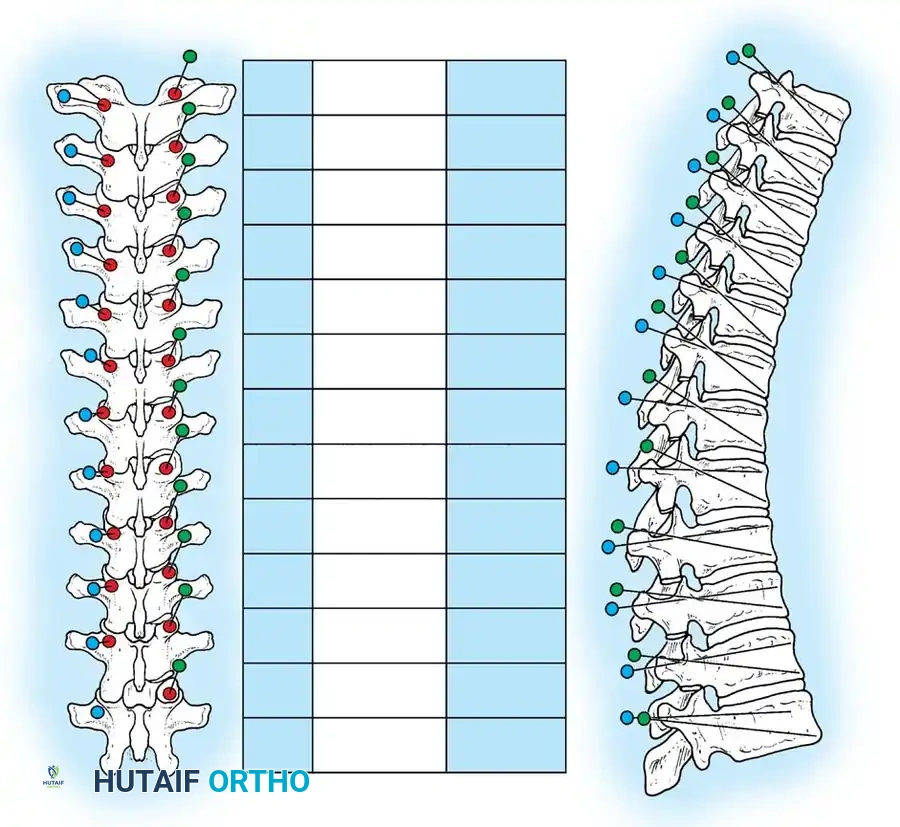

The Moe Technique (Thoracic Spine)

The Moe technique is a highly effective method for achieving intra-articular arthrodesis in the coronally oriented thoracic facet joints.

Fig. 38-26: The Moe technique of thoracic facet fusion, demonstrating the creation of hinged bone flaps.

- Expose the spine fully to the tips of the transverse processes.

- Using a sharp osteotome or Cobb gouge, begin a cut over the cephalad articular process at the base of the lamina.

- Carry this cut along the transverse process almost to its tip. Bend this cortical fragment laterally so it lies between the transverse processes, ideally leaving it hinged on its lateral periosteal attachment to preserve local vascularity.

- Thoroughly denude all articular cartilage from the superior articular process using a sharp curet.

- Make a secondary cut in the superior articular facet, working medially to laterally, producing another hinged fragment.

- Pack the resulting intra-articular defect tightly with cancellous bone graft.

The Moe Technique (Lumbar Spine)

In the lumbar spine, the facet joints are oriented in a more sagittal plane, necessitating a modified approach.

Fig. 38-27: The Moe technique adapted for lumbar facet fusion, addressing the sagittal orientation of the joints.

- Utilize a small osteotome or a needle-nose rongeur to resect the adjoining joint surfaces.

- This creates a distinct rectangular defect within the sagittally oriented joint space.

- Pack this defect forcefully with cancellous bone graft.

- Proceed to decorticate the entire exposed posterior elements (laminae and transverse processes) using Cobb gouges, always directing force away from the spinal canal.

The Hall Technique

The Hall technique offers an alternative method for facet obliteration and grafting, particularly useful in rigid deformities.

Fig. 38-28: The Hall technique of facet fusion, involving sharp excision of the inferior facet and trough creation.

- Sharply amputate the inferior articular facet with a gouge and remove the bone fragment entirely. This exposes the cartilage of the superior facet.

- Remove the exposed cartilage completely with a sharp curet.

- Create a bleeding trough by removing the outer cortex of the superior facet.

- Impact cancellous bone grafts directly into this vascularized trough.

- Complete the procedure with global decortication of the posterior elements.